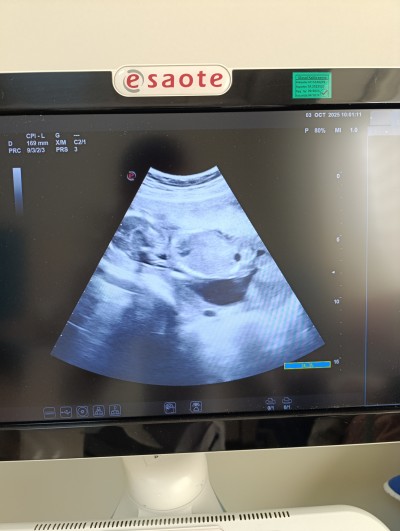

Merhaba kizlar ilk zamanlar özelde doktor ufak bı kanama gözüküyor dedi devlet gittim şuan 4 aylık pihtilasmis igne vuralım dedi yaşayan varmı düşünceleriniz nedir

image

Gebelik haftası 19